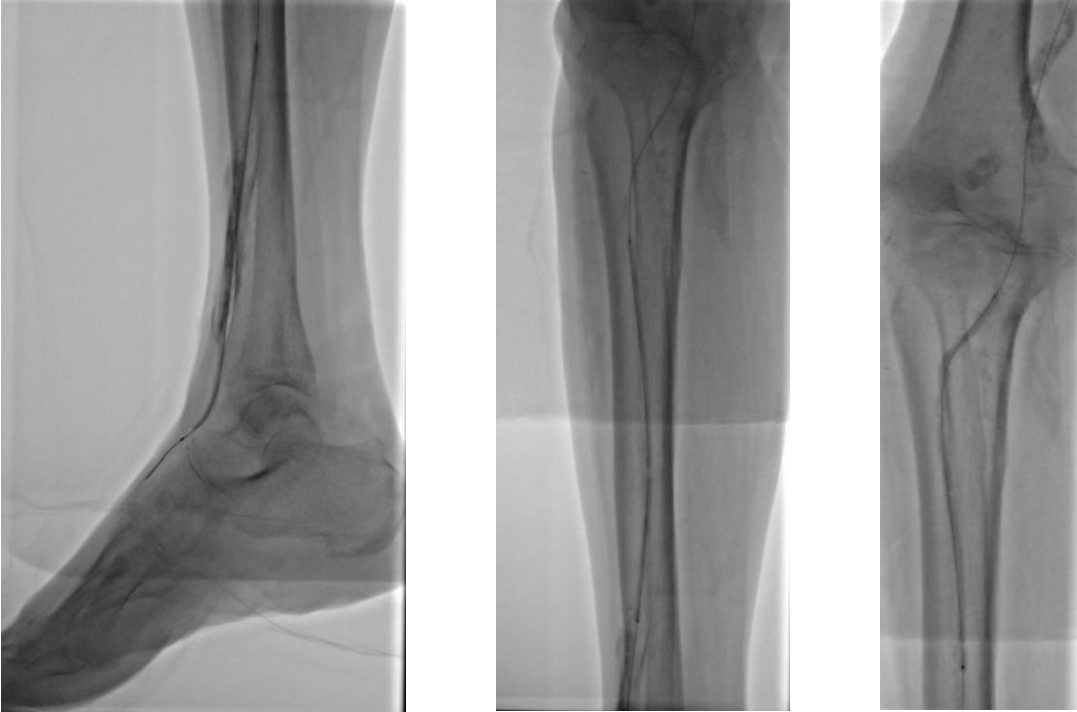

5. 选择6*60mm Shockwave冲击波球囊处理股腘动脉

6. 股浅动脉下段置入6-150mm载药支架,于股浅动脉中上段置入6-220、 6-150mm载药球囊扩张

本例患者股浅动脉重度闭塞,股浅远端重度钙化病变近收肌管,利用Shockwave冲击波球囊获得满意的管腔准备后联合使用DES,为保障远期通畅植入支架,支架膨胀形态理想。

我国患者股浅动脉又多以长段闭塞病变为主,为保障远期通畅率,支架的植入往往不可避免,此时如何优化支架膨胀则至关重要。利用“聚焦式”的冲击波能量作用于重度钙化环最薄弱处,在低压下安全打开钙化斑块,尤其是限制血管床弹性的环形钙化,可有效增加管腔顺应性,减少弹性回缩。